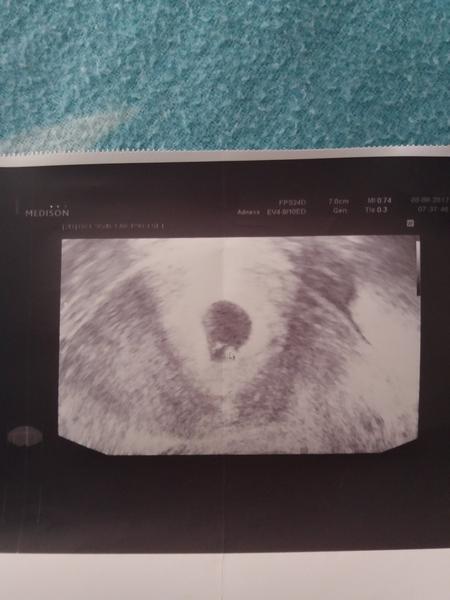

Jsem těhu nebo ne?

Ahoj holky,27.6 jsem mela dostat Ms ale nedostala o mimi se snazime druhym mesicem,delala jsem si dnes 29.6 z rani moci test a byla tam jen jedna/,je mozne ze je to jeste brzo?☹ .Jsem taka nedockava a byla jsem z toho sklamana

Ahoj, mám podobný problém. Taky se snažím druhý měsíc o mimi a MS mi měla přijtí 25.6. a ještě nepřišla. Dělala jsem si test dnes odpoledne a byla tam taky jen jedna čárka. Zkusím to asi ještě zítra ráno, prý to odpoledne není tak účinné, ale jsem jak na trní. :D Do teď jsem mývala MS celkem přesně +-1 den.

Ale abych uz teda aspon prispela, ducha vidim taky a docela pekneho 🙂